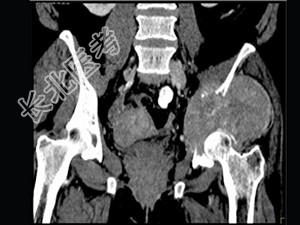

- 单项选择题男,56岁, 肺癌术后2年余,左髋部疼痛, 夜间加重,结合图像, 最可能的诊断是 ( )

B、骨转移